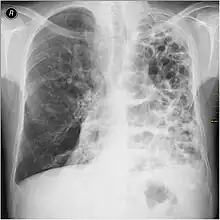

A chest X-ray and complete blood count may be useful to exclude other conditions at the time of diagnosis.[82] Characteristic signs on X-ray are hyperinflated lungs, a flattened diaphragm, increased retrosternal airspace, and bullae, while it can help exclude other lung diseases, such as pneumonia, pulmonary edema, or a pneumothorax.[83] A high-resolution CT scan of the chest may show the distribution of emphysema throughout the lungs and can also be useful to exclude other lung diseases.[25] Unless surgery is planned, however, this rarely affects management.[25] A saber-sheath trachea deformity may also be present.[84] An analysis of arterial blood is used to determine the need for oxygen; this is recommended in those with an FEV1 less than 35% predicted, those with a peripheral oxygen saturation less than 92%, and those with symptoms of congestive heart failure.[24] In areas of the world where alpha-1 antitrypsin deficiency is common, people with COPD (particularly those below the age of 45 and with emphysema affecting the lower parts of the lungs) should be considered for testing.[24]

Chest X-ray demonstrating severe COPD: Note the small heart size in comparison to the lungs.